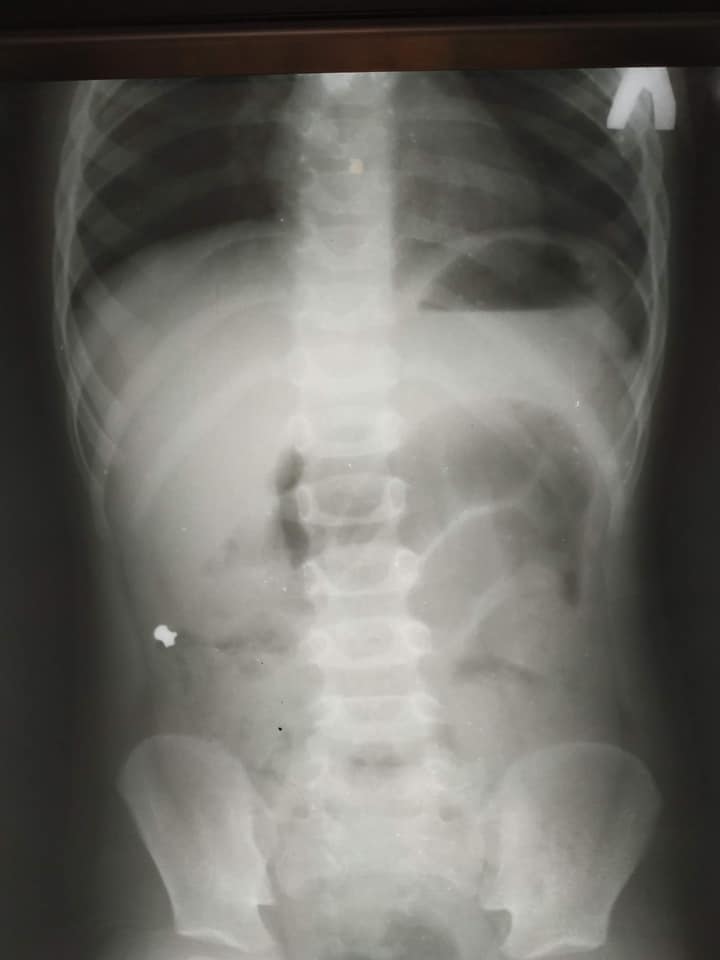

Як повідомляється, до львівського “ОХМАТДИТу” потрапив 6-річний хлопчик з болями в животі. При обстеженні у хірургічному приймальному наші лікарі діагностували гострий апендицит. Дитячий хірург Кирило Лапшин, на чергуванні якого трапилася ця майже детективна історія, не міг уявити, яка знахідка чекає його на рентген-знімку маленького животика. Справа, у клубовій ділянці, чітко візуалізувався сторонній предмет, але дуже дивний. Маленькому пацієнтові від самого початку пощастило, що Кирило Володимирович відразу чітко впізнав обриси кулі від пневматичної гвинтівки. Лікар уточнив у тата хлопчика, чи могло бути, що його син проковтнув кулю. Батько пригадав, що у них вдома справді є пневматична рушниця і до неї металеві кулі. Недавно син грався коробкою з кулями. Ймовірно, випадково хлопчик проковтнув одну з них. І все б нічого, якби куля потрапила зі шлунка в кишківник і вийшла.

У маленького пацієнта куля від пневматичної гвинтівка подолала незвичний шлях – замість потрапити у пряму кишку, куля-мандрівниця опинилася у червоподібному відростку (апендиксі), стала причиною запального процесу у ньому і вклала дитину на операційний стіл.

Хірурги терміново виконали лапароскопічну апендектомію – видалили запалений апендикс через три маленькі проколи у животі. Це малотравматична операція, яка часто виконується у нашій лікарні.

“Коли ми видаляли апендикс, я зразу побачив, що в ньому є потовщення. Ми його видалили і вже назовні розрізали. Там справді була куля! Вона, як стороннє тіло, потрапила з кишок у апендикс і створила його обструкцію. Це і стало незвичайною причиною апендициту”, – розповів дитячий хірург Кирило Лапшин.